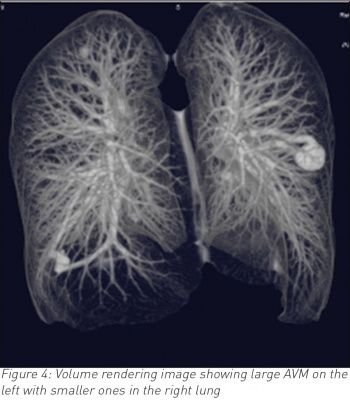

A 35-year-old male, who is otherwise fit and healthy, presented with a 10-day history of cough and temperature. Bloods showed raised white cell count otherwise normal. Chest infection was suspected and a chest radiograph was requested. The latter showed a well-rounded soft tissue opacity in the left midzone with possibly a connecting vessel radiating to the hilum. Two smaller opacities were identified in the right lung. A computed tomography (CT) pulmonary angiogram with intravenous contrast followed and that confirmed the diagnosis of a PAVM of 2cm in the left upper lobe and exquisitely demonstrated the feeding artery and vein with further smaller PVMs of 1cm in the right lung. The patient declined any further intervention.

CT is often the diagnostic modality of choice.3 It differentiates PAVMs from other causes of pulmonary nodules or masses. On CT, the characteristic presentation of a PAVM is a homogenous non-calcified nodule up to several centimetres in diameter or a serpiginous mass connected with blood vessels. Occasionally associated phleboliths may be seen as calcification. Contrast injection shows enhancement of the feeding artery, aneurysmal part and the draining vein.3